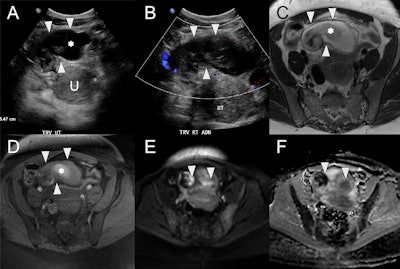

Right pyosalpinx in a 42-year-old female with infectious symptoms and vaginal discharge postspontaneous abortion. (A) Axial ultrasound showing a distended tubular cystic structure (white arrowheads) anterior and to the right of the uterus (U, calipers) with internal echogenic debris (asterisk). (B) Ultrasound demonstrates no color Doppler flow within this structure (white arrowheads). (C) Axial T2w MRI of the uterus with a high signal intensity tubular structure (arrowheads) within the anterior pelvis, corresponding to the right uterine tube and containing intermediate to low signal debris (asterisk). (D) Axial fat-suppressed T1w MRI of the uterus shows high signal debris (asterisk) within the right uterine tube (white arrowheads). Axial high b-value diffusion-weighted image (E) and apparent diffusion coefficient map (F) demonstrate diffusion restriction of internal contents (white arrowheads), which, given the clinical context, is consistent with pus.

In cases of salpingitis, the uterine tubes become edematous with subsequent pyosalpinx. CT may demonstrate thickened uterine tubes (≥ 5mm) with enhancing walls and pelvic-free fluid, they wrote. Pyosalpinx appears as complex internal fluid or a complex cystic mass. Ultrasound may also demonstrate thickened tubes, but it also allows for the detection of hyperemia of the tube or ovary on Doppler imaging.

“A fluid-debris level indicates pyosalpinx. Spillage of pus into the peritoneal cavity allows for spread to the uterus and ovary, resulting in an inflammatory mass, sometimes known as a tubo-ovarian complex. Tubo-ovarian abscesses appear as multilocular septate masses with a thick enhancing wall on CT and as a complex cystic mass on ultrasound and MRI,” the authors stated.

MRI is the most sensitive modality to differentiate pyosalpinx (restriction on diffusion-weighted imaging), hematosalpinx (hyperintense on T1-WI), and hydrosalpinx (hypo- or isointense on T1-WI), they added. “CT and MRI also allow for diagnosis of additional complications such as septic thrombophlebitis and liver capsule adhesions (Fitz-Hugh-Curtis disease).”